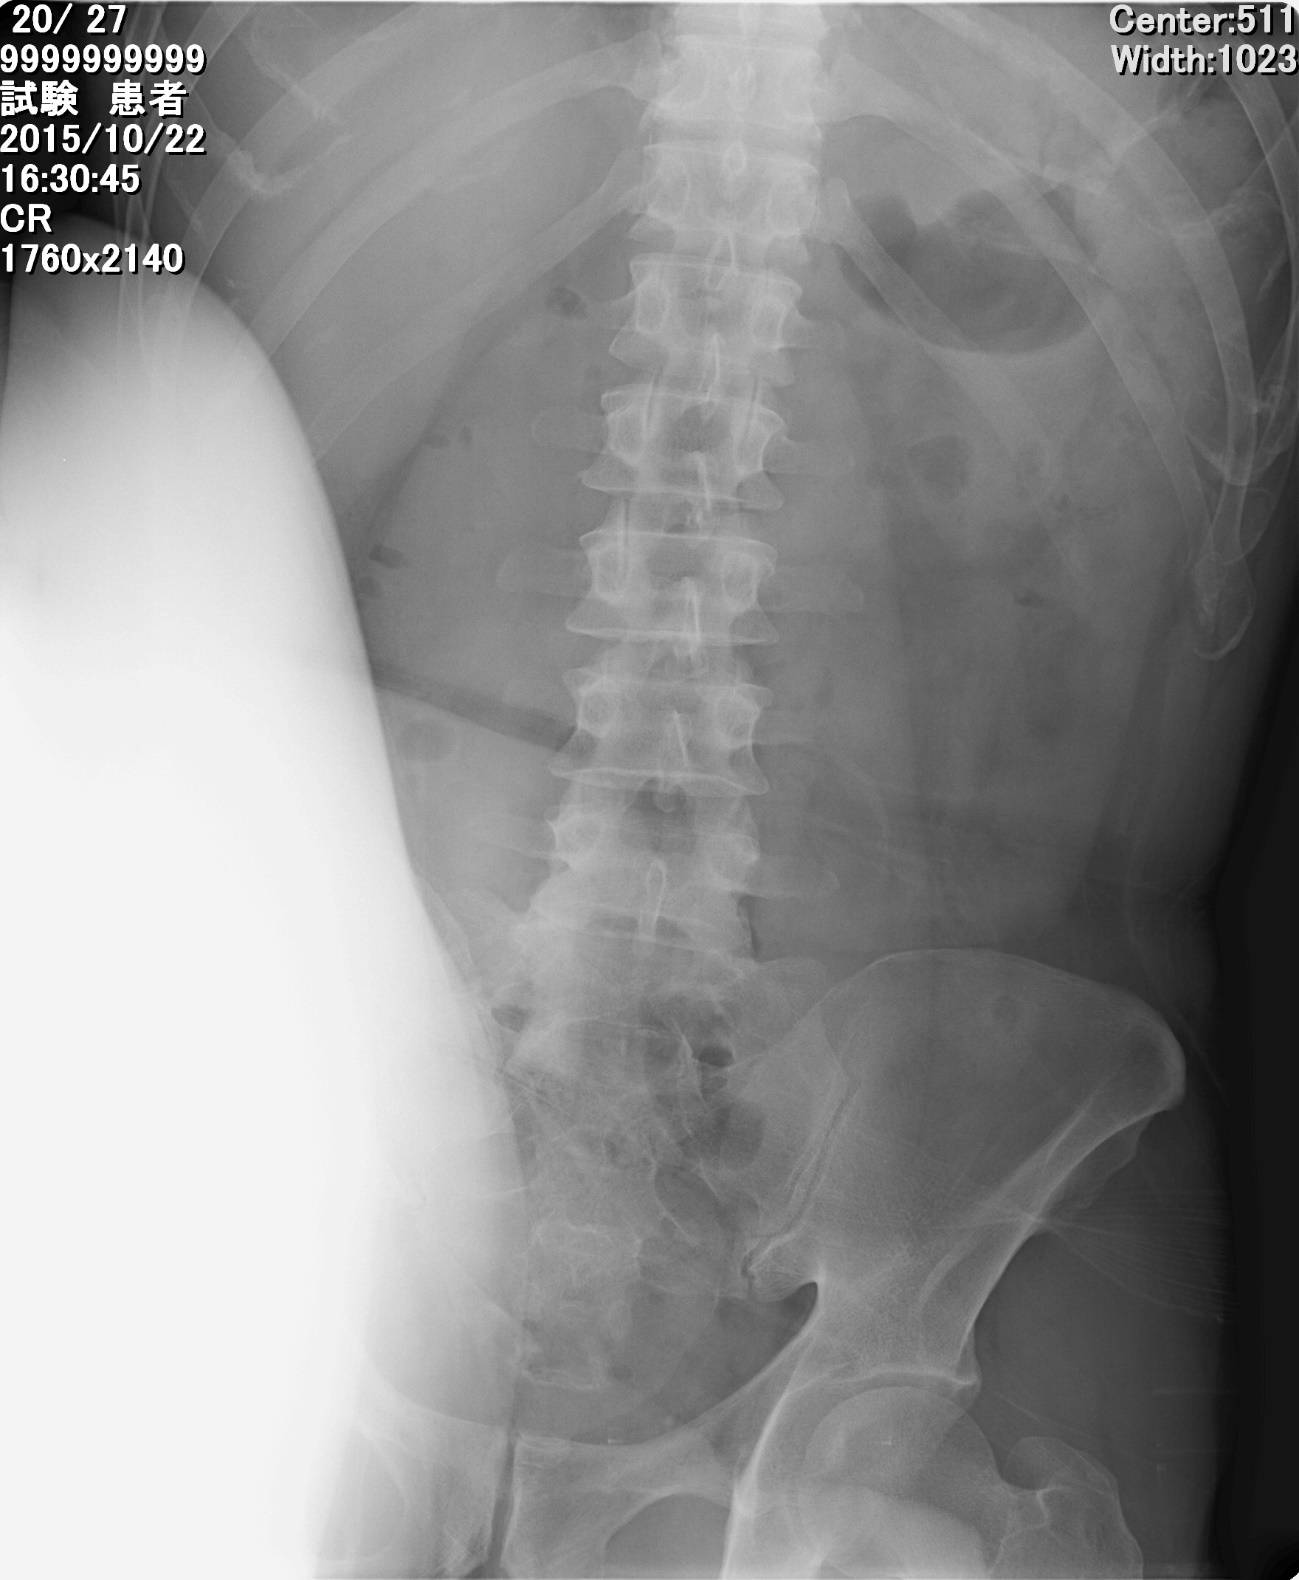

次に真正面ではなく、膝を外側方向に向けて動かした場合、膝の最高点は7番目の胸椎の高さまで到達しました。

このように胸椎にして4つ分の高さに差が出たのです。(あくまでひとりのケースでの結果です)